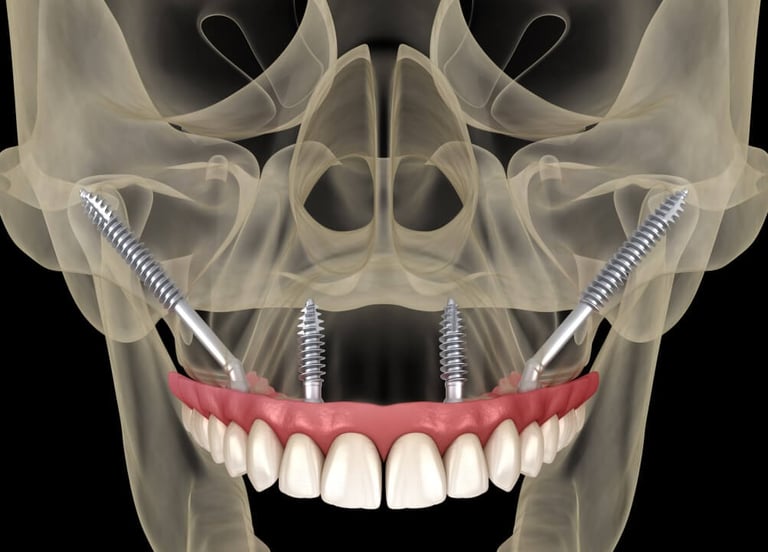

IMPLANTY ZYGOMATYCZNE

W przypadku pacjentów z dużym zanikiem kości, optymalnym rozwiązaniem są implanty zygomatyczne (jarzmowe). Implanty jarzmowe różnią się od tradycyjnych implantów dentystycznych tym, że są zamocowane w kości jarzmowej (kości policzkowej), a nie w szczęce. Mają inny, wydłużony kształt i wymagają bardziej złożonej procedury. Jest to wspaniała alternatywa dla pacjentów, która radykalnie skraca czas rekonstrukcji uzębienia i umożliwia pacjentom cierpiącym na ciężką utratę kości szczęki powrót do normalnej jakości życia. W znakomitej ilości przypadków zęby mocuje się już w dniu zabiegu. Tym sposobem pacjent unika wielomiesięcznego cyklu inwazyjnych procedur przeszczepu kości w celu stworzenia podłoża dla konwencjonalnych implantów.

Dla kogo implanty zygomatyczne?

Warto rozważyć zabieg All-0n-4® z wykorzystaniem implantów zygomatycznych jeśli:

powiedziano Ci, że masz niewystarczającą ilość kości w szczęce i nie kwalifikujesz się do wszczepienia implantów

palisz papierosy nałogowo i leczenie konwencjonalnymi implantami nie jest wskazane (ze względu na duże ryzyko powikłań)

chcesz mieć trwałą alternatywę dla luźnych protez

PRZYGOTOWANIE DO ZABIEGU

Przed umieszczeniem implantów jarzmowych wykonamy badanie TK, dzięki któremu specjalista implantolog precyzyjnie zaplanuje rozmieszczenie implantów. Następnym krokiem jest stworzenie strukturalnego modelu szczęki (tzw. szablonu), który pozwoli ocenić kształt Twojej kości policzkowej oraz szczęki i dokładnie przeprowadzić operację. Zabieg wszczepienia implantów jarzmowych zazwyczaj odbywa się w głębokim znieczuleniu, więc nie będziesz odczuwać bólu ani dyskomfortu. Nad przebiegiem operacji czuwać będzie zespół wyspecjalizowanych medyków z chirurgiem implantologiem i anestezjologiem na czele.